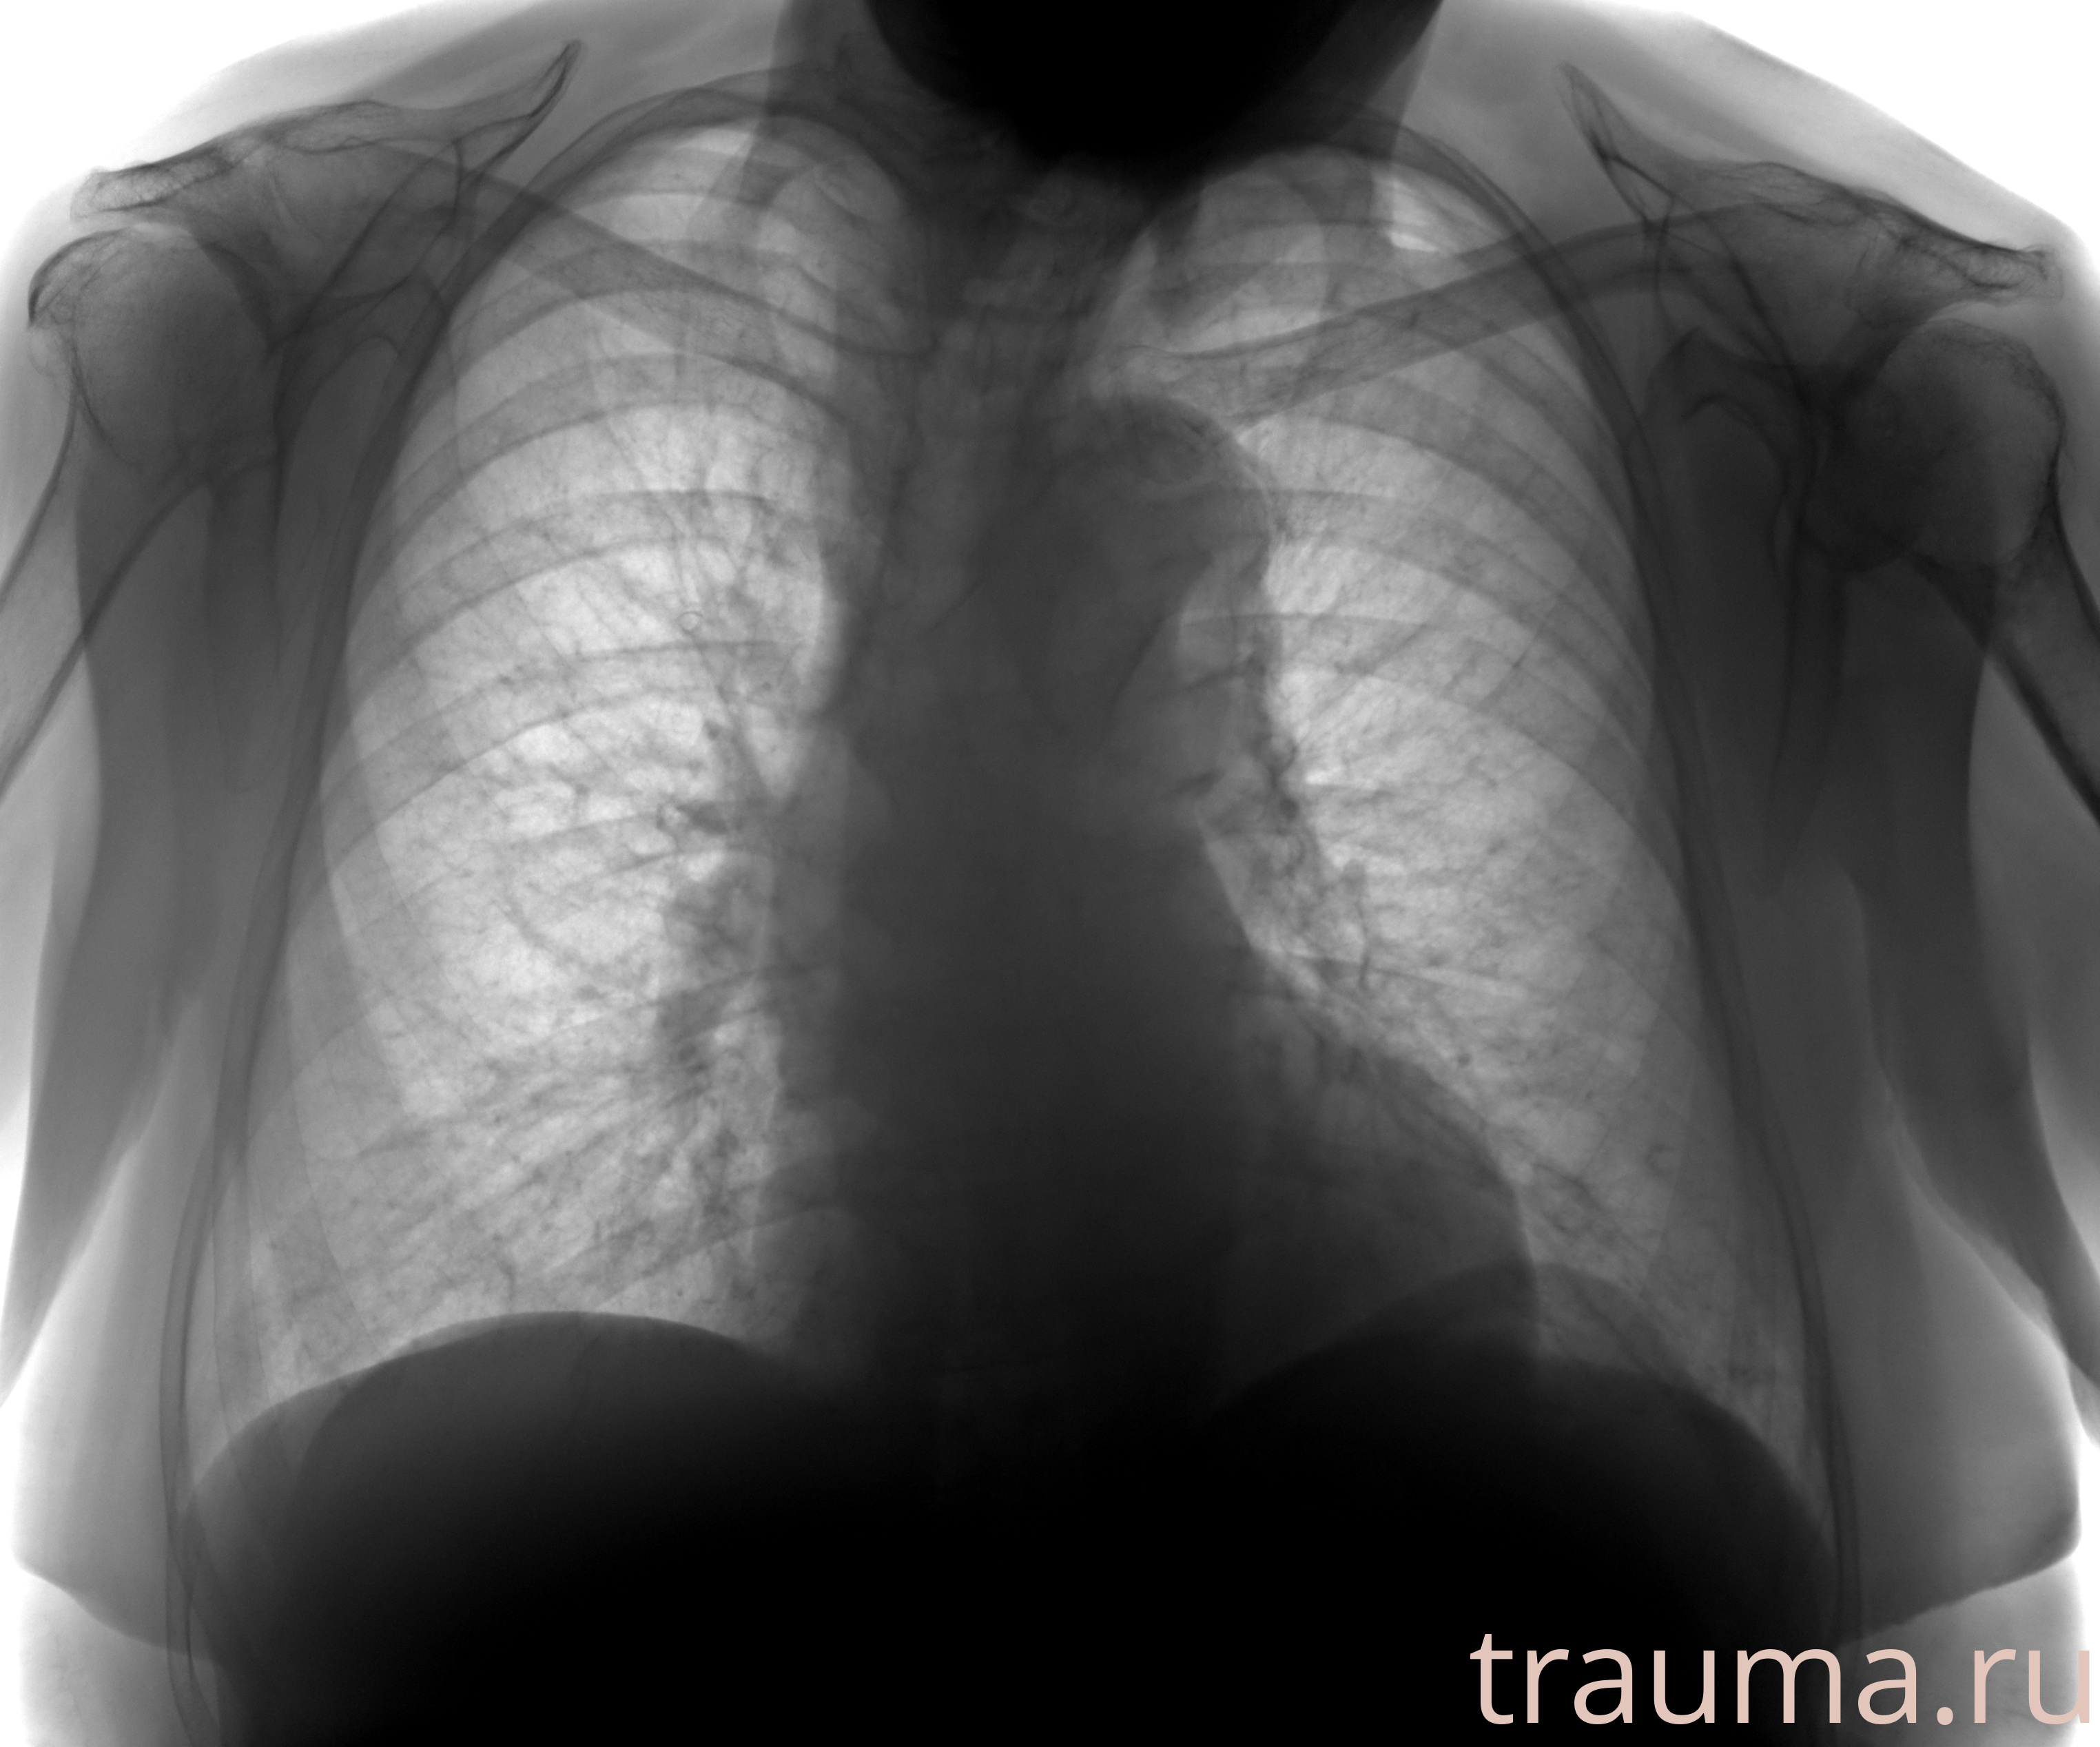

Рентгенограммы

Рентген на дому: по вашему адресу приезжает врач-рентгенолог, травматолог-ортопед с мобильным рентгеновским аппаратом, проводит диагностику травмы или заболевания, делает необходимые рентгенограммы, дает рекомендации по дальнейшему лечению. Получить качественные снимки в домашних условиях возможно благодаря уникальной методике, разработанной МосРентген Центром для института  Склифосовского